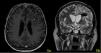

A stereotactic biopsy was made for histological diagnosis. Immunohistochemistry analysis demonstrated that CD20, CD5, and Cyclin-D1 were positive (Figure 2). The patient was re-evaluated with the diagnosis of MCL from the brain parenchymal tissue. PET-CT showed no other involvement rather than the brain parenchyma (Figure 3). The patient, who was diagnosed with isolated CNS MCL, was given MATRix (methotrexate, cytarabine, thiotepa, rituximab) combination chemotherapy, especially known for its efficacy in MCL and CNS lymphoma. On the 8th day of the regimen, the mass was reduced in the cranial MRI (40×34×20 mm) (Figure 4). On the 25th day of the regimen, his alertness increased, he started to communicate in the form of single words. His nutrition and movements improved. The MRI repeated on the 30th and 45th day, the mass was regressed even further (36×25×17mm and 23×22.5×15mm respectively) (Figure 5a,b, Figure 6a,b,c).